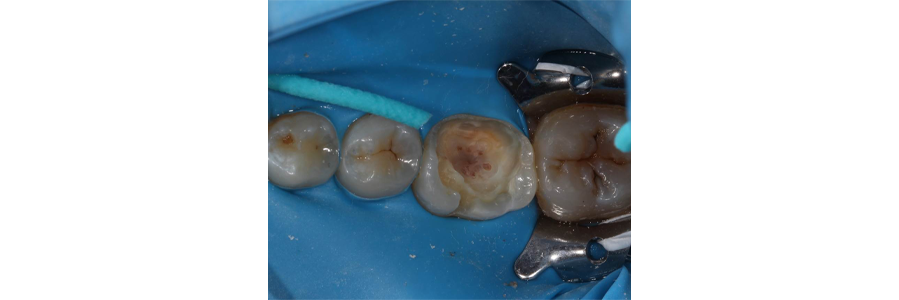

Upon caries excavation, a pulp exposure occurred (Fig. 2).